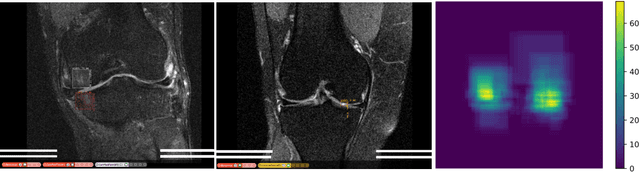

Abstract:Deep Learning has shown potential in accelerating Magnetic Resonance Image acquisition and reconstruction. Nevertheless, there is a dearth of tailored methods to guarantee that the reconstruction of small features is achieved with high fidelity. In this work, we employ adversarial attacks to generate small synthetic perturbations that when added to the input MRI, they are not reconstructed by a trained DL reconstruction network. Then, we use robust training to increase the network's sensitivity to small features and encourage their reconstruction. Next, we investigate the generalization of said approach to real world features. For this, a musculoskeletal radiologist annotated a set of cartilage and meniscal lesions from the knee Fast-MRI dataset, and a classification network was devised to assess the features reconstruction. Experimental results show that by introducing robust training to a reconstruction network, the rate (4.8\%) of false negative features in image reconstruction can be reduced. The results are encouraging and highlight the necessity for attention on this problem by the image reconstruction community, as a milestone for the introduction of DL reconstruction in clinical practice. To support further research, we make our annotation publicly available at https://github.com/fcaliva/fastMRI_BB_abnormalities_annotation.